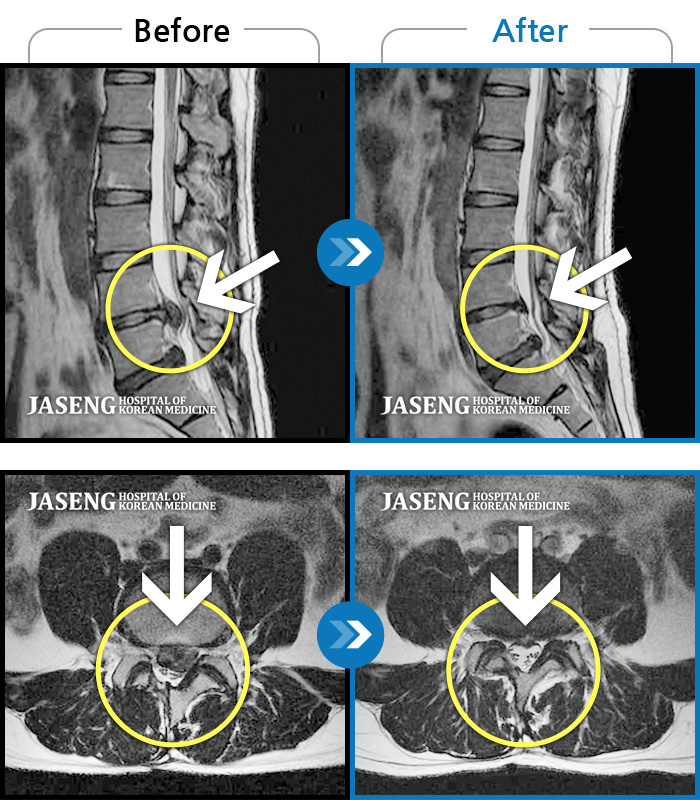

허리디스크

잠실 · 한상욱 원장

우측 엉치부터 우측 다리부터 발끝까지 저리고 아프다. 감각까지 먹먹하다.

촬영시기

2022.04.15 ~ 2022.10.22

2022.12.02